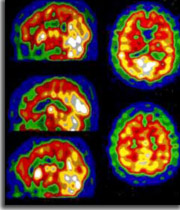

La sclérose latérale amyotrophique (SLA) est une maladie neurodégénérative sévère entraînant une paralysie fatale. Il n’existe toujours pas de traitement efficace. Cependant ces dernières années, les avancées sur le plan clinique et fondamental ont été très nombreuses. Plusieurs travaux ont montré que cette pathologie n’était pas uniquement motrice. Environ 50 % des patients avec une SLA présentent des troubles cognitifs à type de dysfonctionnement exécutif. Sur le plan neuropathologique, la SLA se caractérise par la présence d'inclusions riches en ubicuitine dans le cytoplasme des neurones survivants de la corne antérieure.